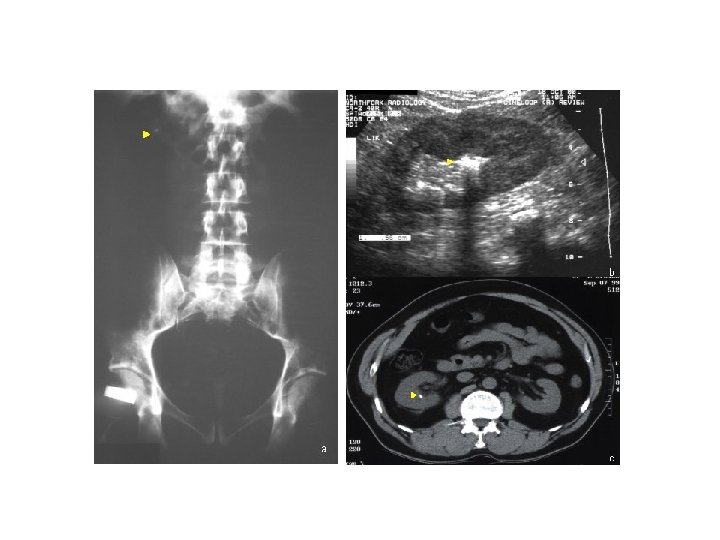

Olgu-1 n Kasık ağrısı ve hematürinin değerlendirilmesinde basit n DÜSG; L 2/L 3 vertebra sağında uzanan büyük bir radyo-opak lezyon incelemelerle genellikle yeterli bilgi edinilebilir n n USG de hiperekojenik lezyonun yukarısında sağ pelvis dilatasyonu (hidronefroz), normal kalınlık ve ekojenitede sağ böbrek Görüntüleme yöntemleri ile üriner akışta blokaja neden olan taş n Renal taşların %90’ı opak olduğundan düz karın grafisi yararlıdır n USG, renal boyut, kitle lezyonları ve dilatasyonlar hakkında bilgi verir 21